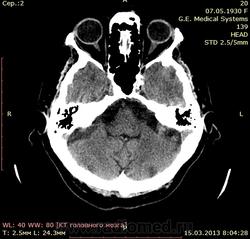

Будьте любезны! Помогите с описанием)) Женщина 1930года рождения поступила в стационар с диагнозом - Повторное ОНМК на фоне атеросклероза и АГ. Сахарный диабет 2 тип.

Попробую, но я не волшебник (тоже только учусь). Слева, перивентрикулярно в бассейне СМА определяются лакунарные инфаркты (или кто поправит- зона пониженной плотности размерами ..х.. мм, плотностью .. ед.Н). Заключение: КТ-признаки подострого ишемического инфаркта в бассейне левой СМА. Правильно?

С лакунарными инфарктами(гиподенсными очагами) может согласен, а что значит гиперденсный очаг в проекции хвостатого ядра?...старый инсульт?..

Как- то не видно лакунарных... Изменения в базальных ядрах слева имеют явно характер дегенеративных, возможно с кальцинозом, расширение переднего рога левого желудочка( относительное!) косвенно это подтвеждает ( по- моему)

Использую термин "зоны патологической плотности". В данном случае, участки повышенной плотности в области базальных ядер левого полушария: головке и теле хвостатого ядра и лентиформном ядре. Более определенно не скажу, судить по джипегу сложновато, дайкомы нужны, но в кровоизлияние не укладывается, передний рог бокового желудочка не компремирован (наоборот, расширен), нет перифокального отека.

По поводу локального снижения плотности белого вещества у передних и задних рогов боковых желудочков - это лейкоареоз. Более правильно лейкоараиоз, но в русскоязычной литературе сложилось как-то так.

а возможно, что  очаги патологической плотности это признакт старого нарушения мозгового кровообращения? В анамнезе у пациентки было ранее ОНМК...

Гиперденсные очаги слева в проекции базальных ядер, что это такое? Кровь? Обызвествление?

Написала бы петехиальное кровоизлияние? базальных ядер слева

- и на КТ-контроль через неделю. Контроль всё и прояснит. Остальные изменения старые и неинтересные.

Это не может быть признаком " старого нарушения". Старое - это всегда понижение плотности, вплоть до плотности ликвора.

"Заключение: КТ-признаки петехиального кровоизлияния базальных ядер слева. КТ- контроль через неделю. Лейкоареоз лобных долей. Гидроцефалия? "